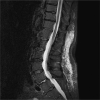

Case presentation: In this article, we report a rare case of durvalumab-induced triple-M syndrome in a 69-year-old woman with stage III lung adenocarcinoma. She was admitted with profound generalised muscle weakness, myalgia, and exertional breathlessness, about a week into her second cycle of durvalumab, an immune checkpoint inhibitor. She had clinicopathological features of myositis, myasthenia and myocarditis with acute onset symptomatic tri-fascicular block on electrocardiogram, requiring urgent cardiology intervention. Durvalumab was discontinued and she was treated with a combination of high-dose steroids and intravenous immunoglobulin after which she had clinical and biochemical improvement, albeit with residual muscle weakness.

Figures